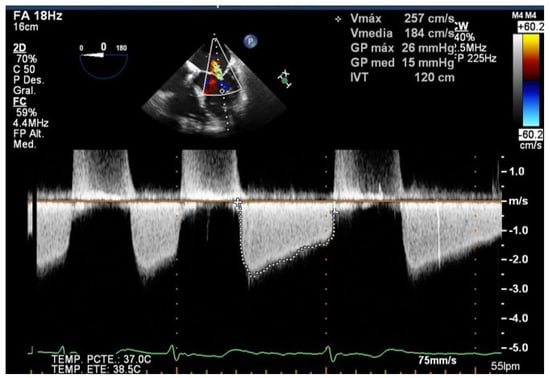

The echocardiographic criteria to diagnose SLDA are the color Doppler demonstration of significant MR through the leaflet interface, new excessive leaflet mobility following device deployment, and a lack of diastolic tissue bridge by 3DTEE; acute changes in pressure also occur with the new appearance of the v-wave after the initial improvement after clip implantation (Figure 5). Once the complication has occurred, the TEE undoubtedly helps in determining the mechanism of the loosening of the leaflet by measuring the portion of the free leaflet with respect to the measurement prior to implantation [13]. Other mechanisms, such as tear or perforation, can be viewed as a disruption of leaflet integrity reaching the leaflet edge or not, respectively. An excessive clip–leaflet tension can be shown as a shape distortion affecting leaflet coaptation, without disruption of the leaflet integrity. The entrapment of the clip in leaflets or subvalvular structures with chordal rupture appears in TEE as new excessive leaflet mobility [1]. Chordal entanglement should be avoided by minimizing device manipulation below the mitral valve and not advancing the system deep into the left ventricle.

Figure 5.

Two-dimensional transesophageal echocardiogram showing a very severe mitral regurgitation after the partial detachment of a clip and a leaflet tear prolapsing in the left atrium (yellow arrow). Three-dimensional transesophageal echocardiogram in the enface mitral view, where a clip can be seen attached to the anterior leaflet (red arrow) and loose from the posterior with a lack of diastolic tissue bridge. In the lower panel, simultaneous recording of left atrium (green), pulmonary artery (yellow), and aortic pressure (purple): baseline, post clip implantation and after detachment.